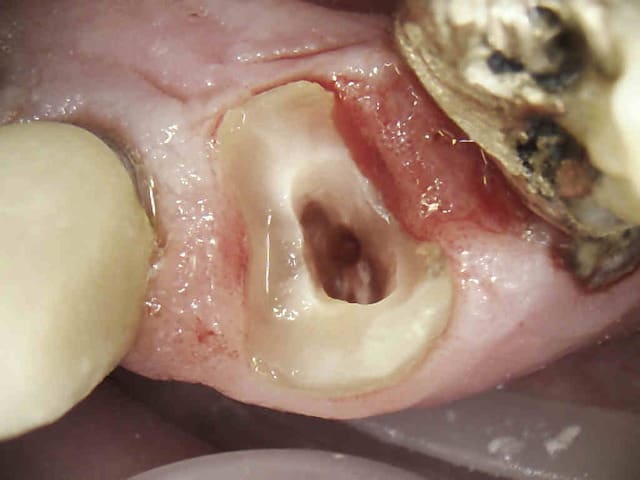

Je viens de tailler, alors des conseils de ma part pour ceux qui cherchent des réponses comme moi j'en cherchais ça fait une semaine :

- Vérifier la taille de la fraise avec une fraise cylindrique de la même taille (ou une taille proche) des fois les vendeurs n'ont aaaaauuuuucune idée de ce qu'ils vendent ou ce sont des dentistes qui croient qu'on utilise la même chose qu'eux.

- pour tailler en parallélisme ( les sillons guides et pour les relier) il faut déjà voir le parallélisme, donc ne pas faire comme moi et prendre la fraise entre les yeux et la dent pour tailler, la fraise doit être tangente à la ligne de plus grand contour (ça a l'air tout bête mais j'en ai mis du temps pour le comprendre) et les yeux de préférence à hauteur de la ligne de plus grand contour.

- on demande une double angulation en P et en V, il faut tailler les ces faces avec des fraises conique bien sur, mais dont la longueur est inférieure, ça permet de préserver la double angulation et éviter de les retailler.

- pour éviter de foirer le collet, tailler au dessus du collet, puis le repasser avec une fraise cylindrique, vous dites tous la boule mais ils nous demandent une ligne de finition avec un angle droit, donc la cylindrique, mais ça dépend de ce qu'on demande. Aussi, le collet présente des concavité et des convexités coronaires (respectivement sur les faces Vestibulaires/palatines et proximales) donc il faut suivre le contour en deux temps (quand ça monte et quand ça descend ou l'inverse)

J'ai essayé de résumer ce que la plus part d'entre vous faites les yeux fermés ou par pur instinct, ça donne ça, la photo n'est pas tellement claire mais on arrive à voir la ligne de finition quand on regarde de haut, donc ça veut dire qu'à priori il y a dépouille ( de 6 degrés j'espère)

Si vous avez quelque chose à corriger ne vous gênez surtout pas, de même si vous avez quelque chose à rajouter.